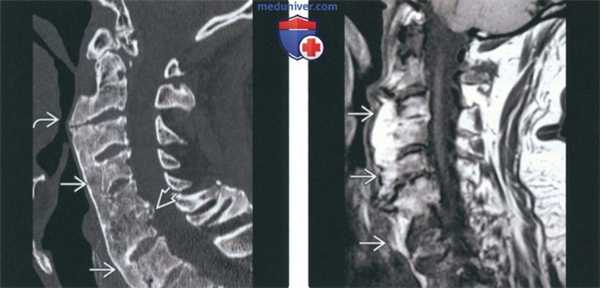

(Слева) Рентгенография в сагиттальной проекции: типичное наплывающее костеобразование, позволяющее диагностировать ДИСГ. Обратите внимание на то, что пространства дисков практически сохранены, однако на уровне С5-С6 визуализируется небольшое сужение. Значительных изменений в дугоотростчатых суставах не определяется. У пациента отмечается сильная боль в шее.

(Справа) МРТ, сагиттальная проекция, режим Т2 с подавлением сигнала от жира: у этого же пациента подтверждается наличие переднего костного образования, содержащего костный мозг. Тем не менее, дополнительно визуализируется грыжевое выпячивание диска на уровне CS-C6, которое является причиной боли в шейном отделе. Для ДИСГ не характерно наличие выраженного болевого синдрома, поэтому следует осуществить поиск других его причин. Патологические изменения диска и перелом с псевдоартрозом могут являться этиологическими факторами развития радикулопатии или миелопатии. Дисфагия является результатом формирования костного образования спереди. (Слева) МРТ, сагиттальная проекция, режим Т1. признаки ДИСГ. Исследование выполнено в правой парасагиттальной проекции. Передняя наплывающая оссификация выражена здесь в гораздо большей степени, нежели слева (не показано). Переднее костное образование берет начало непосредственно из центра тел нескольких позвонков и из нижнего и верхнею отделов тел других позвонков. И то и другое характерно для данною заболевания. Диски, а также дугоотростчатые суставы остаются неизмененными. ДИСГ не является истинной артропатией, однако в ряде случаев сочетается с дегенеративным поражением позвоночника.